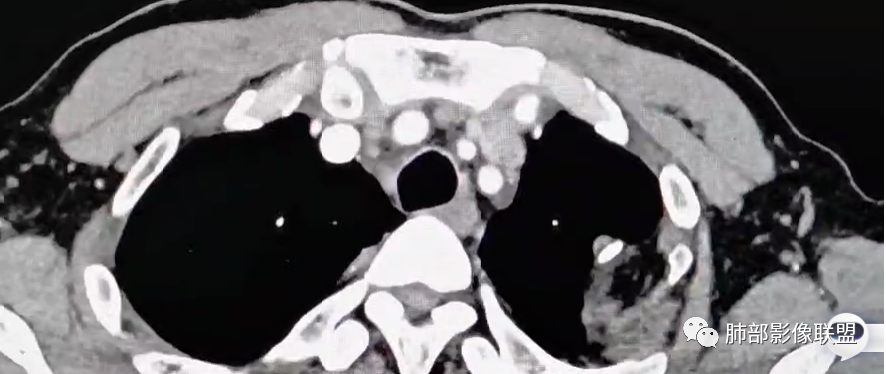

右上叶前段胸膜下新发病灶;纵隔淋巴结较前增大

增大淋巴结

很多增大的淋巴结,强化方式一致均匀,

未见明确坏死,融合不明显,没有明确的分布优势。

平扫。这种淋巴结密度偏高,还是挺多这种略高密度淋巴结的

2、思路,支气管分叉处的这种锐角突起,邻近胸膜脂肪间隙密度模糊,加上老师们标记的其他征象,猜炎性在前